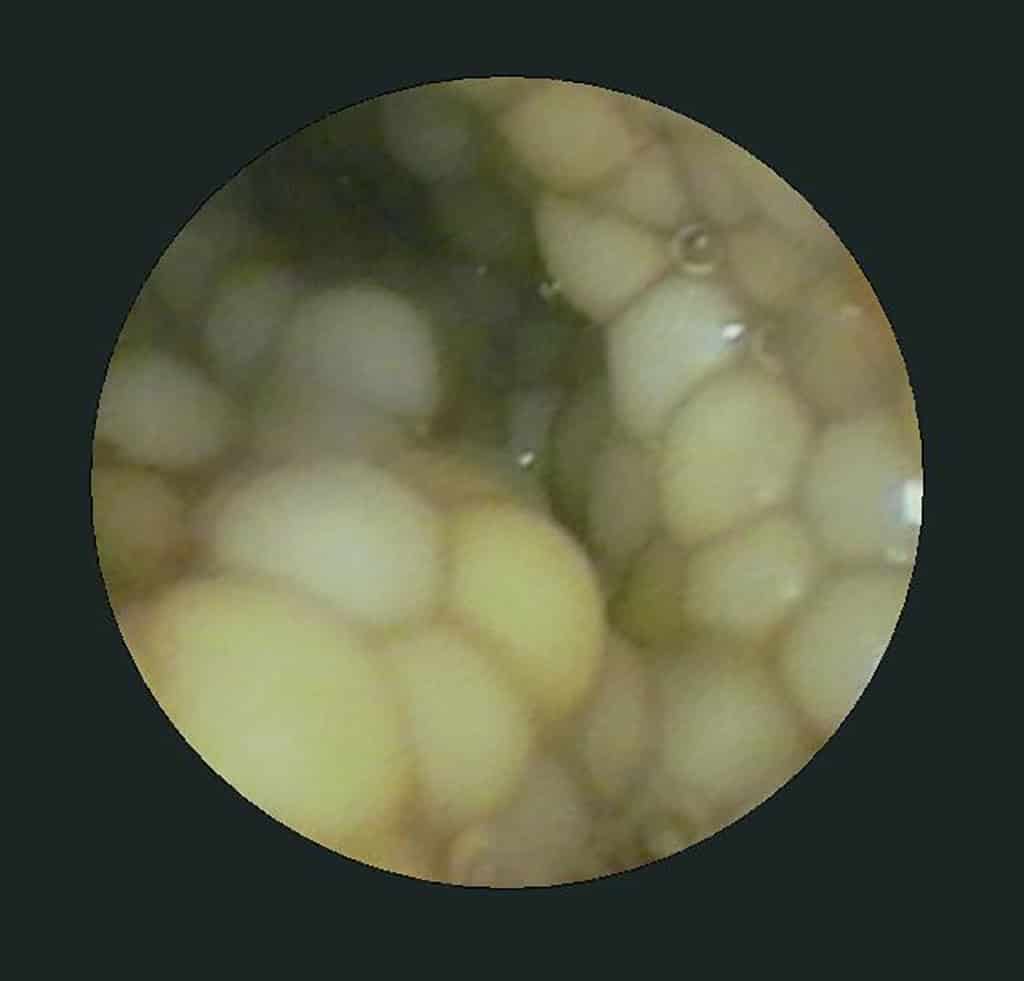

Endoscopie is in de eerste plaats zeker een interessante manier om het geslacht van je koi te weten te komen. Bij geslachtsrijpe vrouwtjes zie je mooi het kuit zitten als gele bolletjes in een tros bij elkaar. Mannetjes daarentegen hebben een witte geslachtsklier die naargelang hun rijpheid klein tot zeer groot is. Frequent voorkomende aandoeningen van het geslachtsstelsel kunnen langs deze weg snel onderkend worden. Zit een vis nu bijvoorbeeld met een tumor van de eierstokken, of is het (versteend) kuit dat de buik zo doet opzetten? Zulke zaken kunnen nu perfect in beeld gebracht worden. Vooral bij een groot volume aan kuit in de buik dient men evenwel op te letten zodat er geen organen beschadigd worden. Door het inblazen van lucht of kooldioxide langs een speciale ingangspoort die voorzien is op het toestel (of via een zogenaamde veress naald die op een ander plaats in de buik gebracht wordt), eventueel zelfs een steriele fysiologische zoutoplossing om de zichtbaarheid nog te verbeteren, vergroot men de ruimte die men tracht te inspecteren en verkleint men de kans om letsels van organen te veroorzaken.